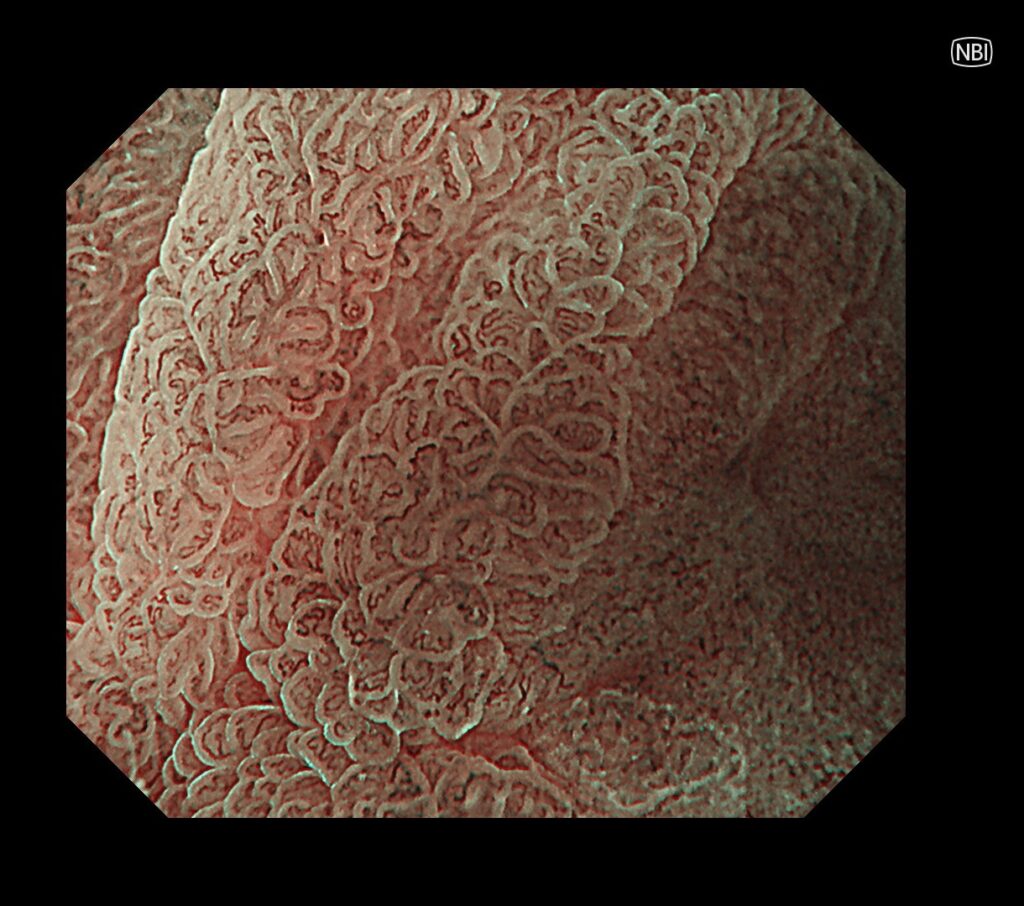

拡大観察で癌血管を全周性に視認できます。やはり、癌部:茶色、非癌部:緑色として観察されます。